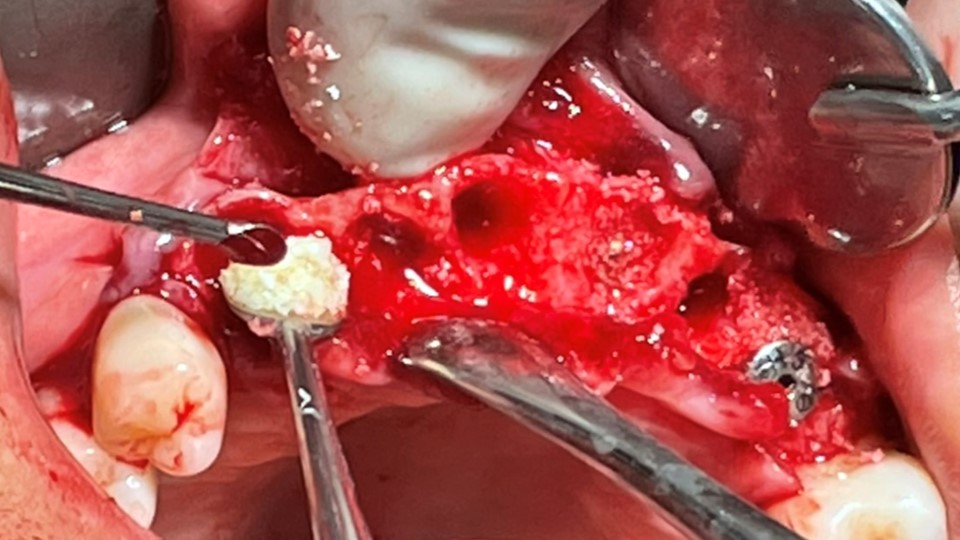

▲Implant placement GBR

▲GBR(Xenograft).